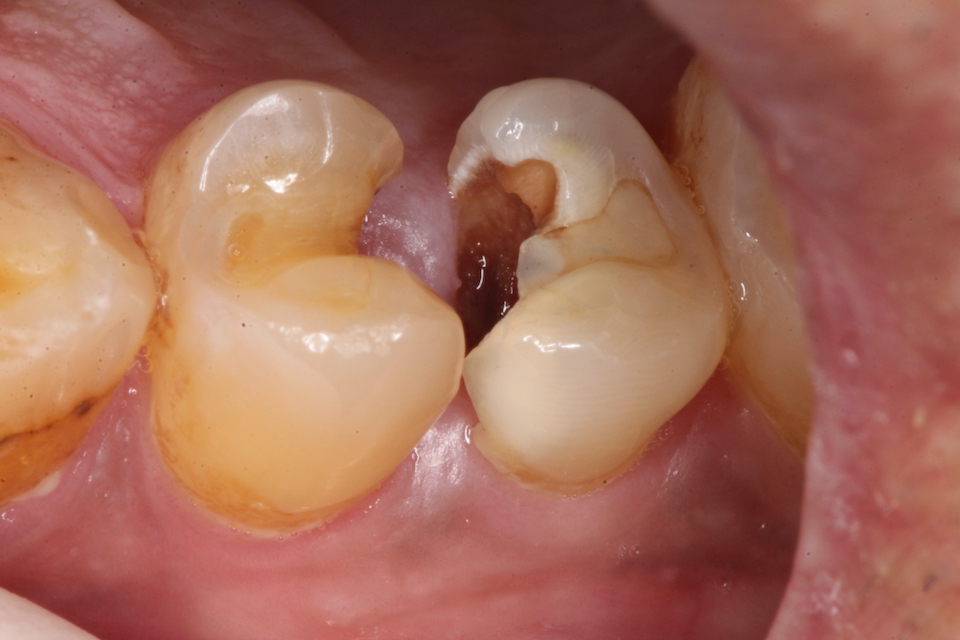

下顎7番の頬側歯茎部カリエスの原因 2025.06.04